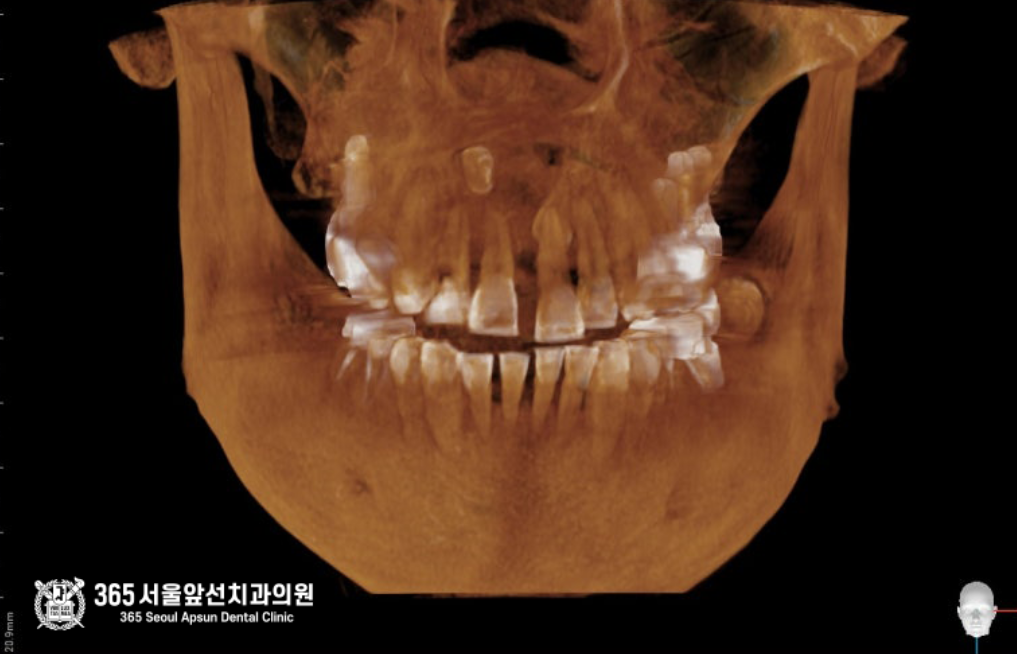

3차원 CT 영상 소견입니다. 구강내 기준으로 오른쪽 앞니 상방으로 과잉치아가 보이며, 과잉치아 주변에 매우 큰 낭종이 있습니다. 인접한 다른 치아의 입천장쪽으로도 과잉치가 매복되어 있으며, 다행히 해당치아는 낭종을 형성하지는 않았던 상태입니다. 촬영일시 : 2024.05.02. 정면 ct 사진입니다. 코 아래쪽으로 2개의 과잉치아가 매복되어 있으며 매우 큰 낭종도 보입니다. 2개의 매복과잉치와 코 아래의 낭종을 동시에 제거하는 수술과 동시에, 왼쪽 아래턱에 심하게 충치가 진행된 치아를 발치하고 임플란트를 식립하는 수술까지 진행했으며 수술시간은 총 36분에 걸쳐서 순조롭게 진행되었습니다 ㅎㅎ 촬영일시 : 2024.05.02. 과잉치 발치와 낭종 적출술을 동시에 진행하고 있는 모습이며, 가장 오른쪽 사진은 적출된 낭종과 과잉치입니다. 낭종과 심하게 진행된 치주염으로 인해 앞니 두개 치아는 발치를 해야하는 상황이었으며, 낭종 제거 후 6개월 이상 기다렸다가 뼈의 회복이 진행되면 임플란트 식립을 하기로 했습니다 ㅎㅎ 촬영일시 : 2024.12.10. 아래쪽 임플란트 수술까지 합쳐서 총 36분에 걸쳐서 순조롭게 진행되었으며, 환자분께서도 만족하셨던 증례입니다. 촬영일시 : 2025.02.14. 대략 6개월 후 보철까지 모두 완료된 엑스레이 사진입니다. 아무리 복잡하고 어려운 치료라도 자신있습니다. ㅎㅎ 부담갖지 마시고 내원해주시면 최선을 다해 치료하겠습니다. 오늘은 도화동치과 365서울앞선치과에서 매복된 과잉치와 그로인해 생긴 낭종을 제거한 증례를 소개해드렸습니다. 앞으로도 좋은 치료 증례로 찾아뵙겠습니다 ! [ 치료기간: 2024년 5월2일 ~ 2025년 2월 14일 ] ※ 365서울앞선치과의원의 모든 포스팅은 각 진료과 의료진이 직접 작성합니다. 365서울앞선치과의원 블로그의 임상 케이스 게시물은 환자분께 의학적으로 정확하고 상세한 정보를 드리기 위해 각 진료과 의료진이 직접 작성하며, 모든 증례 사진은 본원 의료진이 직접 시술한 증례를 촬영한 것으로, 의료법 제23조, 제56조에 의거하며 환자분의 동의를 얻어 포스팅에 사용하였습니다. 또한 해당 케이스는 본 환자분의 치료 결과이며, 환자 상태에 따라 치료의 결과는 달라질 수 있습니다. |